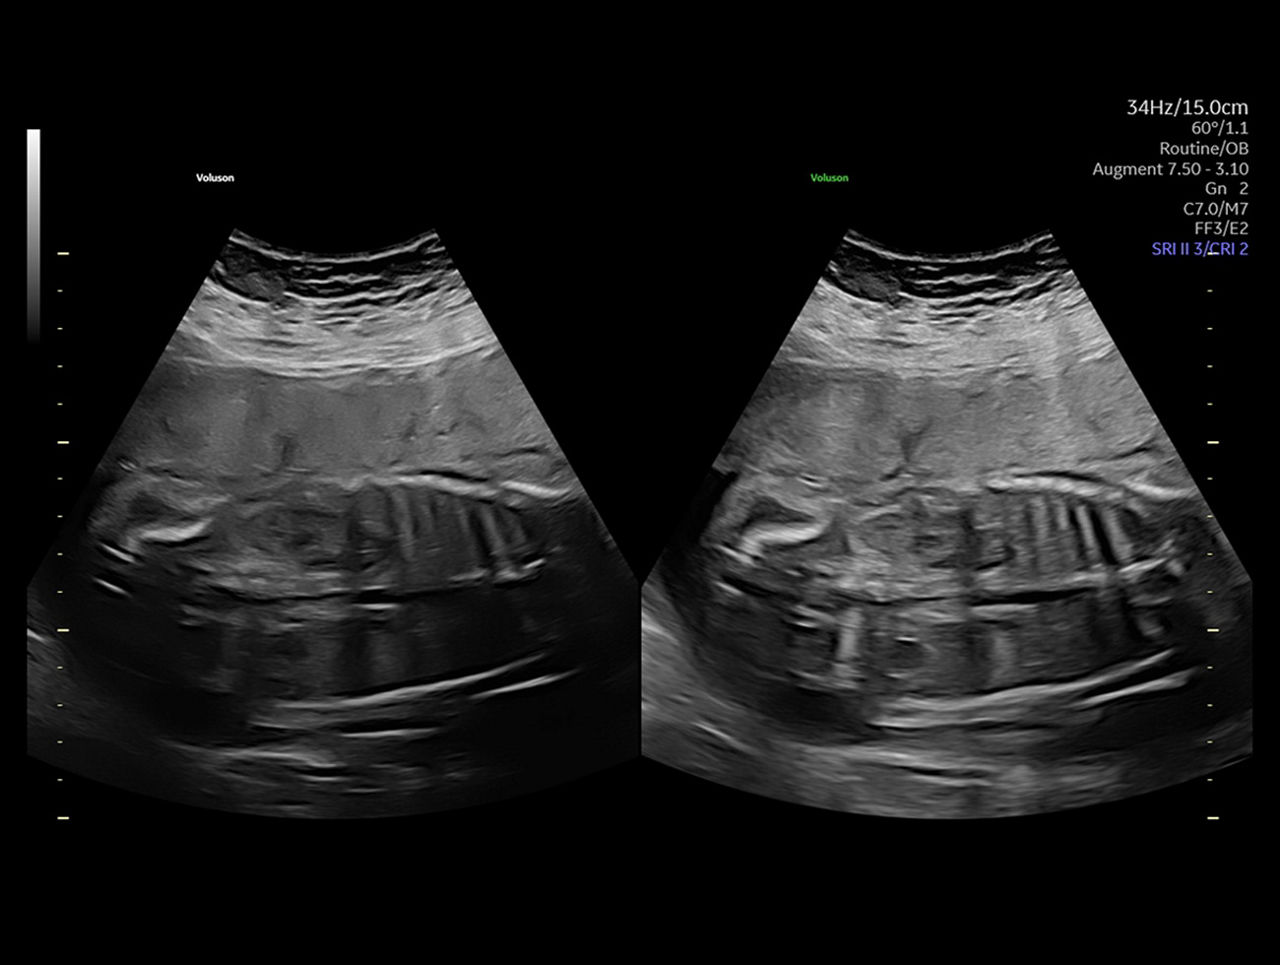

Augment

Solve Challenging Scans

Utilize our Augment feature to reduce noise and increase penetration for a robust, cleaner image even in difficult to scan situations like high BMI.